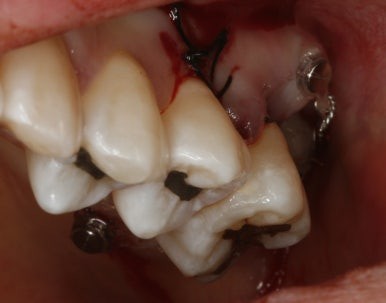

공교롭게도 이 환자도 27세 여성환자...

늘 열심히 일하고 야간진료 때 컴퓨터 가방을 들고 오던 환자였다.

일도 힘들었을텐데 꼬박 꼬박 진료도 잘 와줘서 사랑니가 원래 제 자리였던것처럼 위치하고 있다.

비용도 수고로움도 임플란트만큼이지만 치주인대를 갖고있는 나의 치아로 대체할 수 있음은 충분히 투자가치가 있다는 개인적인 의견이다...